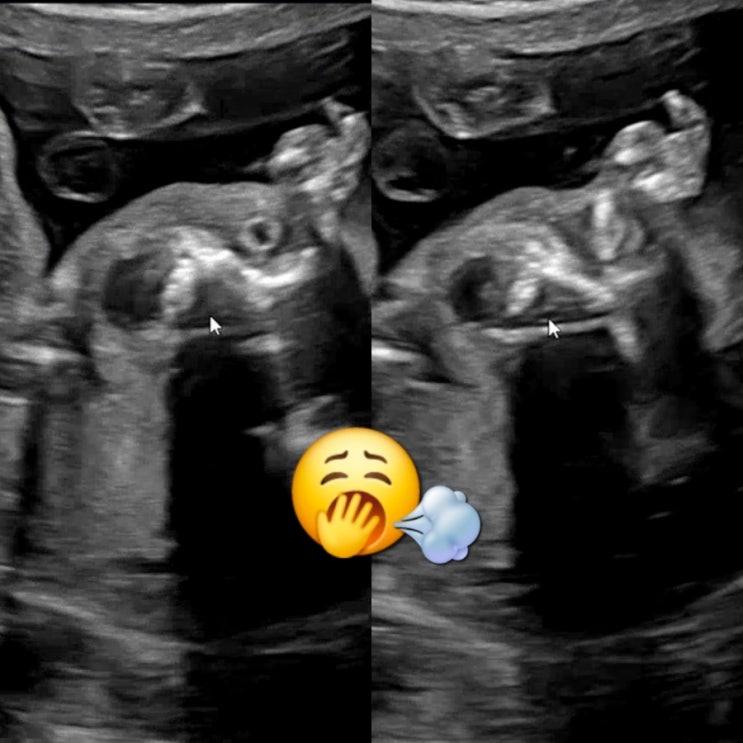

25년 1월 웨이트(3) 하품쩌억 31년산 엄마와 21주 기쁨이

사업하는 부모를 만나 벌써부터 바쁘다바빠 현대인의 삶을 알아버린 기쁨이. 엄마가 피곤하면 아기도 피곤...